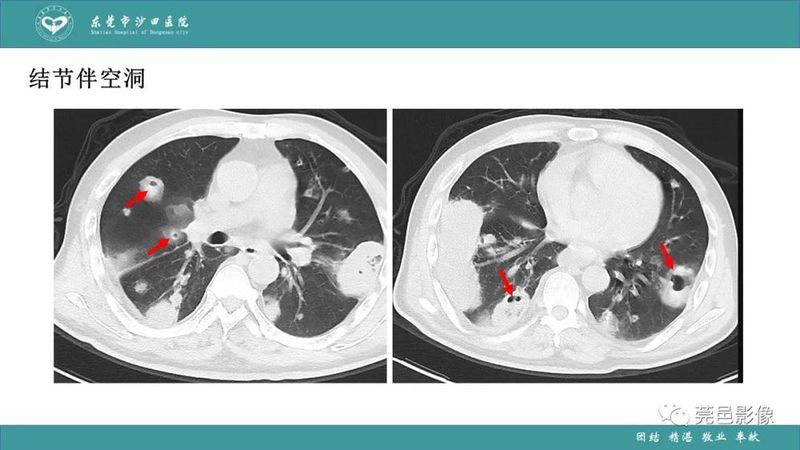

「肺炎克雷伯杆菌肺炎」影像学诊断+鉴别诊断